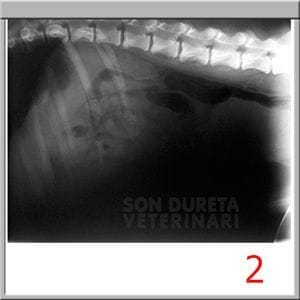

Rápidamente lo trajeron al Servicio Veterinario de Urgencias de la Clínica Veterinaria Son Dureta. Pancho llegó con un shock hipovolémico, (falta de oxígeno en órganos y tejidos debido a la pérdida tan grande y aguda de líquidos y sangre) sus mucosas estaban muy pálidas, su pulso era débil y su temperatura corporal muy baja. Se realizaron analíticas, donde no se identificaron órganos internos dañados aunque las enzimas hepáticas estaban alteradas y por supuesto, las alteraciones del sistema digestivo asociadas a su estado.